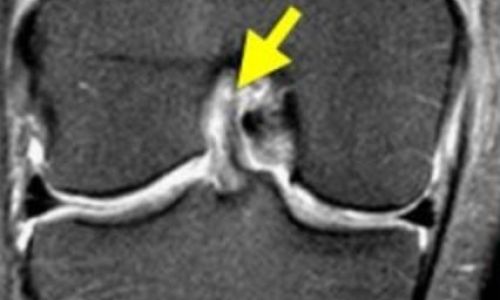

Εμφανίζεται συχνά σε νέους αθλητές στα πλαίσια αθλητικής κάκωσης ενώ παράλληλα μπορεί να εμφανιστεί και σε άτομα μεγαλύτερης ηλικίας με εκφυλιστική αιτιολογία (ηλικιακή φθορά).

Η διάγνωση γίνεται κλινικά μετά από τις κλινικές δοκιμασίες του ορθοπεδικού (π.χ. test Mcmurray) και η τελική επιβεβαίωση γίνεται μετά από απεικονιστικό έλεγχο με μαγνητική τομογραφία γόνατος.

Η ρήξη μπορεί να αφορά είτε τον έσω μηνίσκο (συχνότερα σε άτομα μεγαλύτερης ηλικίας) είτε τον έξω μηνίσκο (συνήθως η ρήξη αυτή συνυπάρχει με ρήξη πρόσθιου χιαστού συνδέσμου).

Η θεραπεία είναι είτε χειρουργική (αρθοσκοπική συρραφή μηνίσκου ή αρθοσκοπική μηνισκεκτομή) είτε συντηρητική αντιμετώπιση. Η απόφαση για το είδος της θεραπείας γίνεται πάντα μετά από συζήτηση και λεπτομερή ανάλυση του ορθοπεδικού ιατρού με τον ίδιο τον ασθενή λαμβάνοντας υπ' όψιν παράγοντες όπως η ηλικία του ασθενούς, το είδος της ρήξης, τα συμπτώματα που οδήγησαν τον ασθενή να ζητήσει βοήθεια καθώς και το επίπεδο αθλητικής δραστηριότητας του ασθενούς.